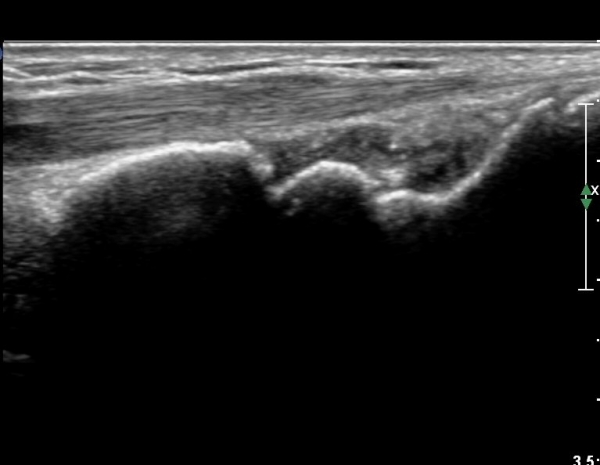

ŽÃÍÀÚ¸¦ ¾à°£ ôÃ÷À¸·Î À̵¿ÇÏ´Ï ¿ä°ñ ¸»´Ü¿¡ ÇÇÁú°ñ ¿¬°á¼º ¼Ò½Ç(loss of cotical continuity)ÀÌ °üÂûµÊ(»çÁø 2, 3).

¿ä°ñ Ⱦ´Ü¸é°Ë»ç¿¡¼­ lister's tubercle ̫̿¿¡¼­ ÇÇÁú°ñ ¿¬°á¼º ¼Ò½Ç(loss of cotical continuity)ÀÌ °üÂûµÊ(»çÁø 4).